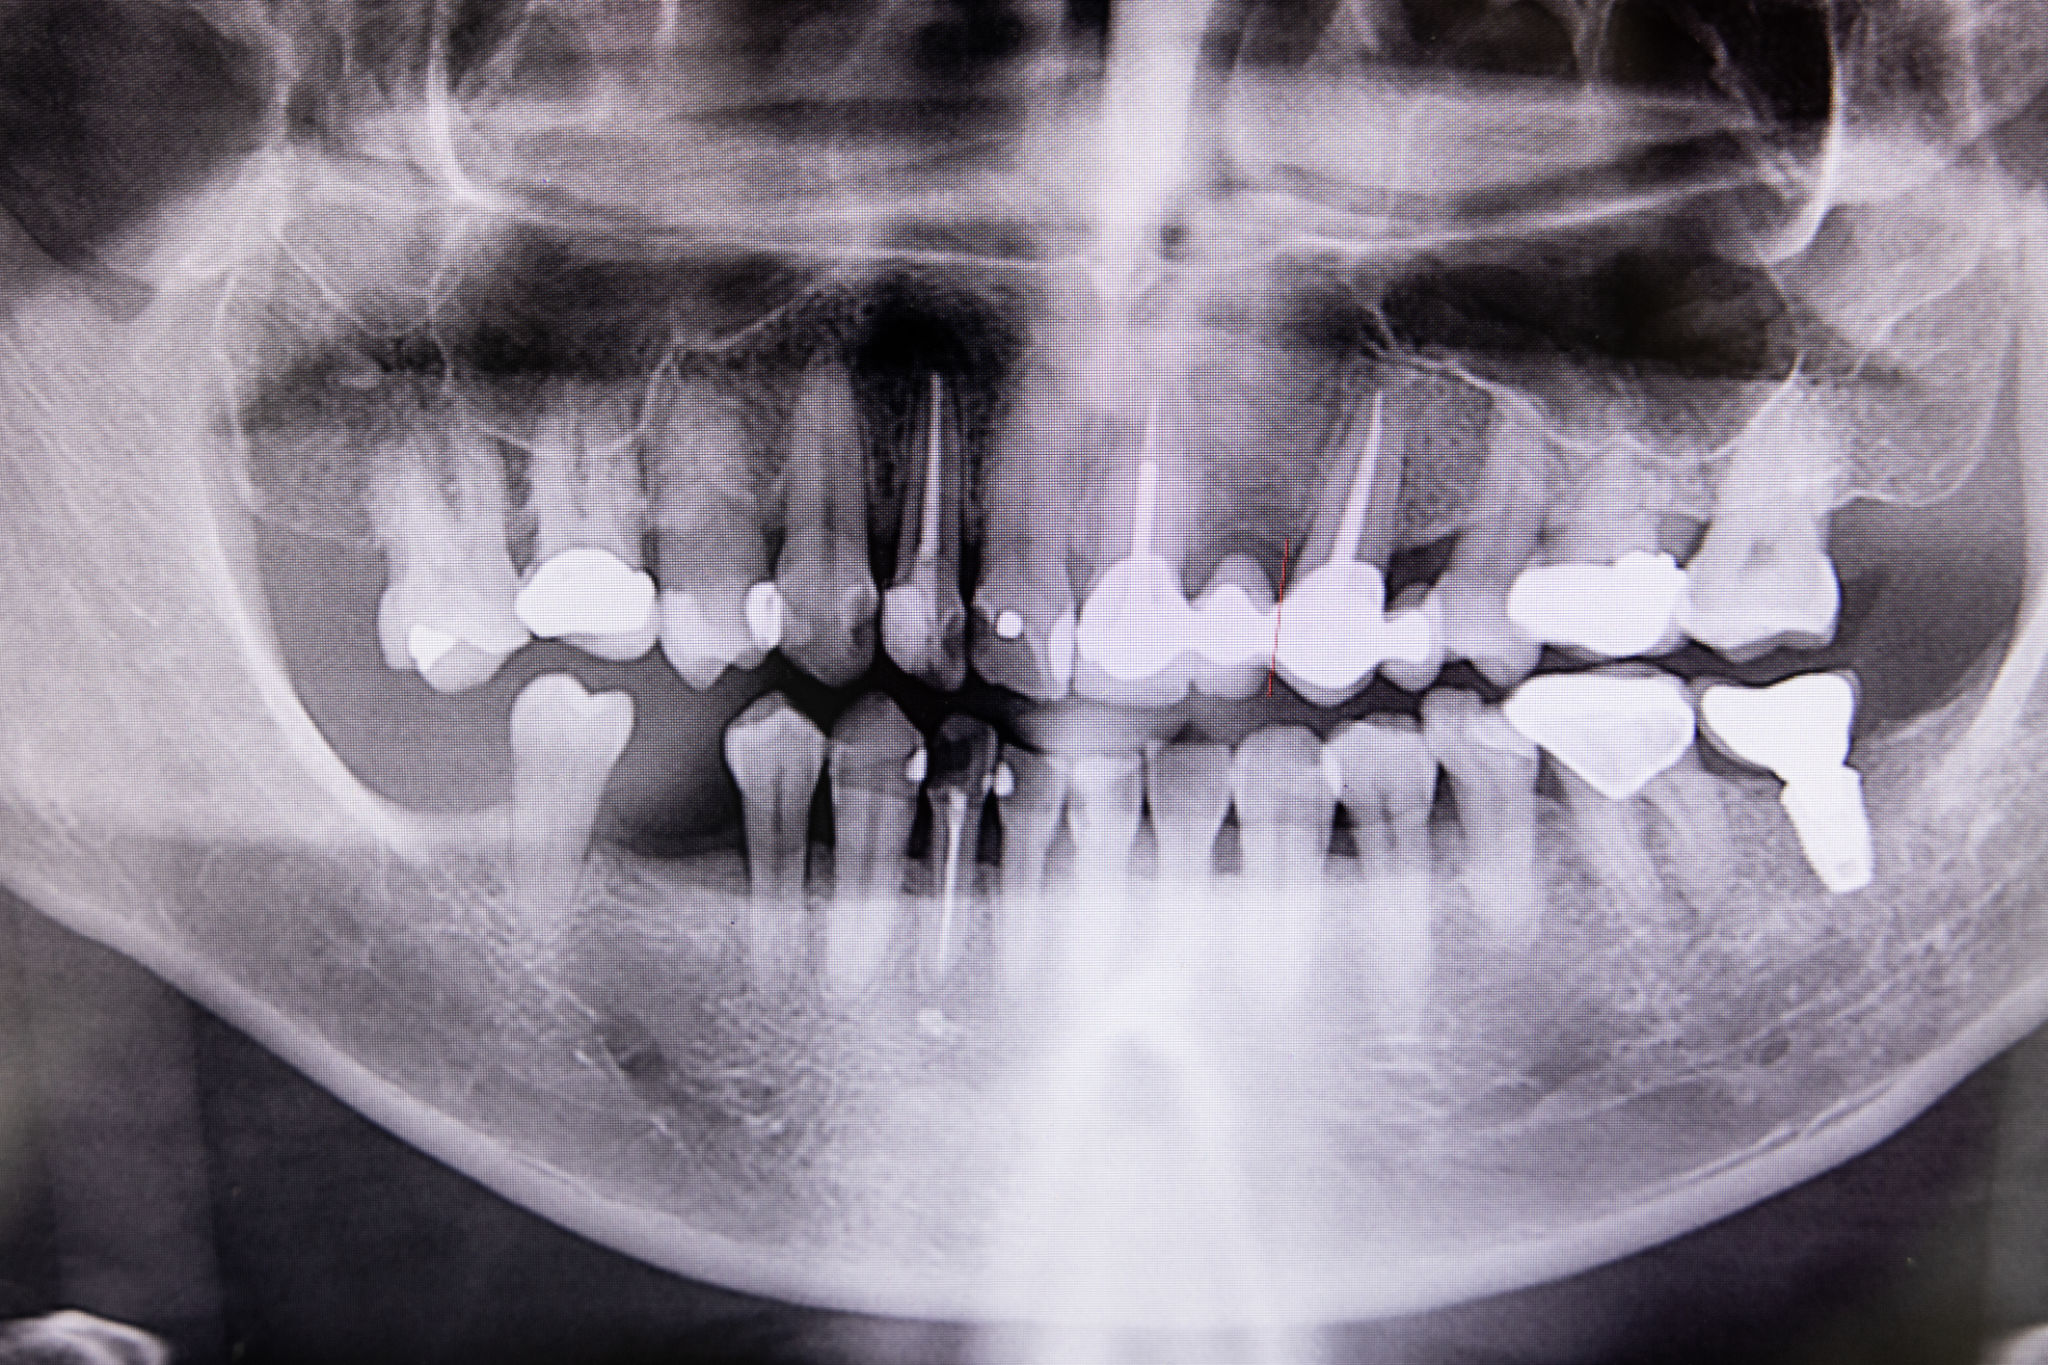

Oral Surgery in Amarillo, TX

Oral surgery is any surgery to treat the mouth, jaw, teeth, gums, or supporting structures. Oral surgery can include extractions, such as removing wisdom teeth, performing dental surgery to correct jaw alignment or treat sleep apnea, etc.